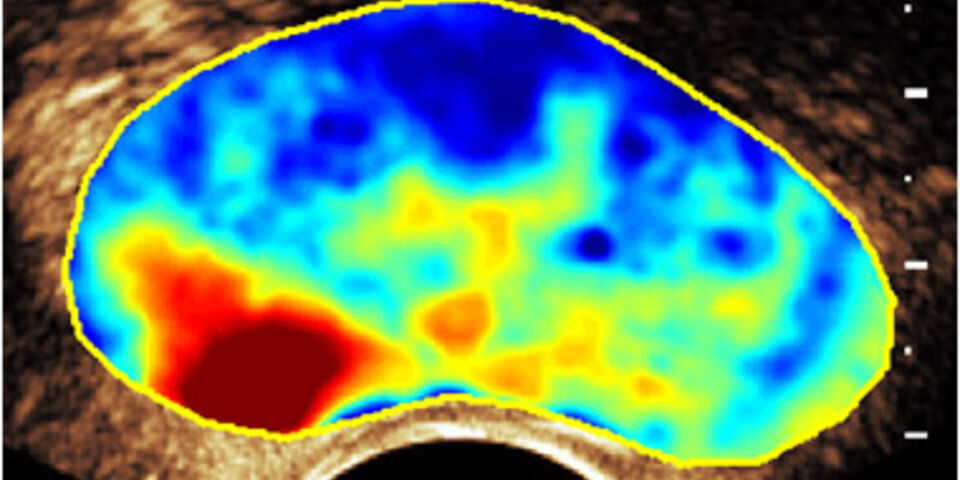

Onderzoeksleider Massimo Mischi van de TU Eindhoven ontwikkelde een manier om te zien of en waar iemand prostaatkanker heeft, op basis van bestaande ultrasound scanners. Dit zijn apparaten die met geluid in het lichaam kijken, net zoals de echoapparatuur bij zwangerschapsonderzoek. Maar deze apparaten zien normaal gesproken geen verschil tussen gezond weefsel of tumorweefsel. Om dit toch zichtbaar te krijgen, maakte Mischi gebruik van het feit dat tumoren heel veel kleine bloedvaatjes aanmaken, in een typisch patroon, om te kunnen groeien. Bij patiënten wordt eenmalig een contrastvloeistof ingespoten met minuscule bubbels, die de ultrasound scanner ziet tot in de kleinste bloedvaatjes aan toe. Met geavanceerde beeldanalysetechnieken, die het typische bloedvatenpatroon van tumoren herkennen, genereert de computer vervolgens een nauwkeurig beeld waarop eventuele tumoren te zien zijn. Het onderzoek duurt maar een minuut, en maximaal tien minuten later is de uitslag er al. Bovendien is het onderzoek veel goedkoper, doordat de dure analyse van de biopten niet meer nodig is.